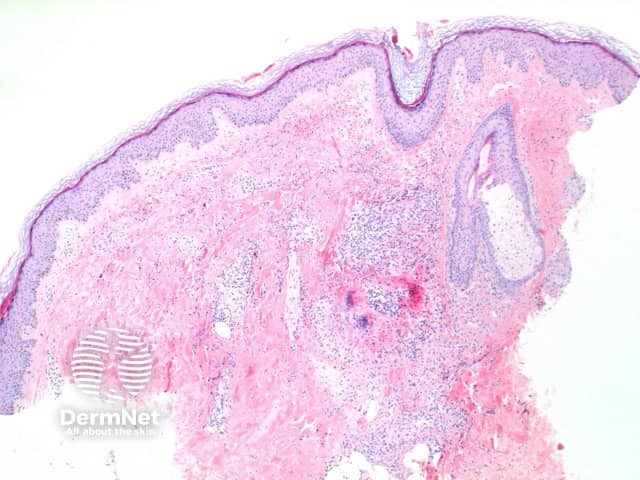

The histological features of bullous pemphigoid are:

Subepidermal bulla

Direct immune fluorescence